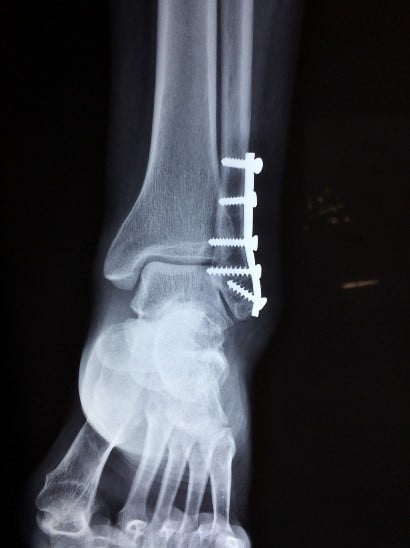

Por ejemplo, en muchos casos es necesario hacerse pruebas diagnósticas: radiografías, resonancias magnéticas, ecografías… son muy habituales para determinar el alcance de una lesión concreta.

✔Una operación (o varias) quirúrgica…